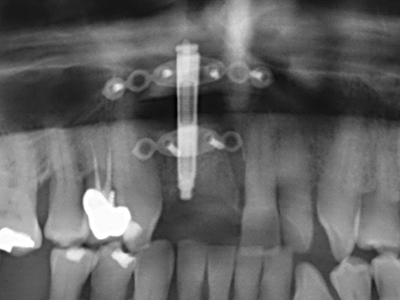

Фиг. 11: Следоперативната панорамна снимка показва вертикалната аугментация и синус лифта.

Фиг. 15: Прегледът на рентгеновата снимка след 1 година показва стабилно състояние на нивото на костта.